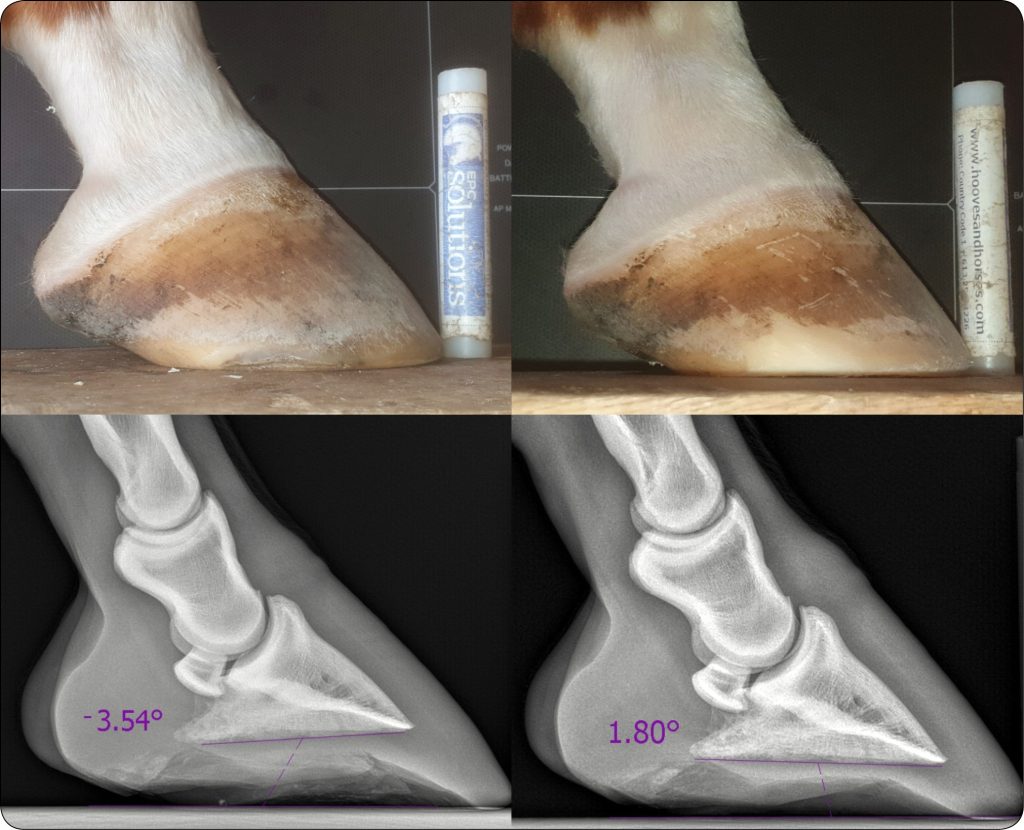

Pierwszym krokiem jest zmiana sposobu strugania i zdarza się, że jest to wystarczające. Najważniejszą zasadą przy struganiu kopyt z niskim kątem podeszwowym jest NIESTRUGANIE kątów wsporowych – lepsze są te podwinięte, a dające wysokość z tyłu kopyta, aniżeli gdy nie ma ich w ogóle. Według doświadczenia autorek obawy, że kąty wsporowe położą się jeszcze bardziej, jeżeli nie będzie się ich cofać do podstawy strzałki, są w zdecydowanej większości przypadków nieuzasadnione (ryc. 3). Kolejna istotna sprawa to obniżenie przodu kopyta przez usunięcie rogu podstawowego i podeszwy. W sytuacjach wątpliwych, gdy istnieje ryzyko zbytniego pocienienia podeszwy, należy przeprowadzić korekcję pod kontrolą RTG. Po wstępnym wystruganiu należy wykonać RTG kopyta, skalibrować zdjęcie i zmierzyć, czy jest jeszcze materiał do dalszej korekcji kąta (ryc. 4).